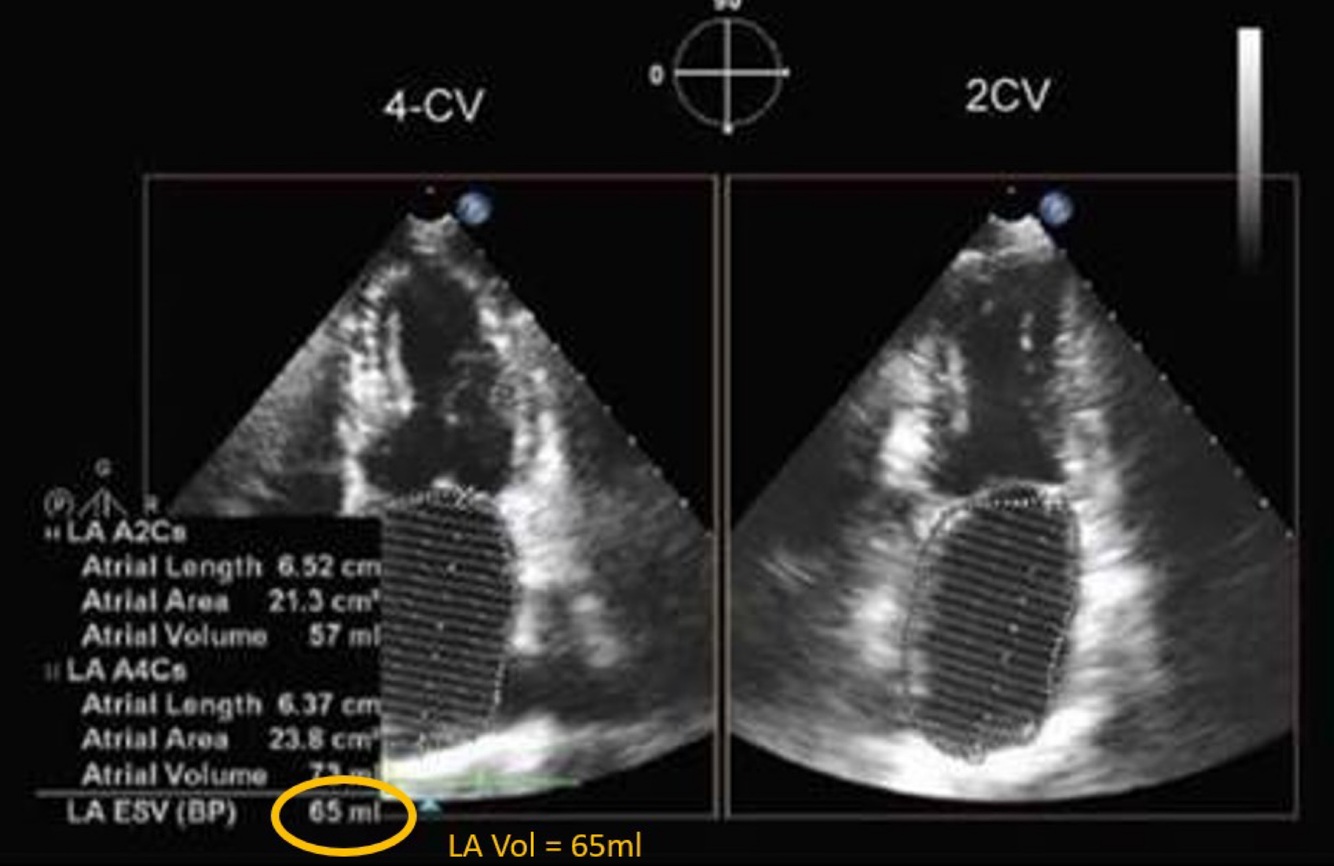

Q

Classify the patients LAVI. Patient BSA = 1.8

A

Mildly dilated

LA vol index = 65/ 1.8 BSA = 26ml/m

Normal LAVI = 16-34 ml/m2- this is just over that = mild

Severely enlarged is >48ml/m2